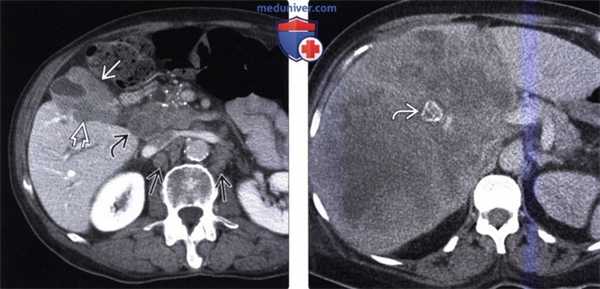

(Слева) На рисунке показан рак желчного пузыря в виде объемного образования в ограниченном участке его стенки, прорастающего в печень и обусловливающего обструкцию общего печеночного протока. В просвете желчного пузыря видны множественные конкременты.

(Справа) На корональной КТ с контрастным усилением визуализируется мягкотканное объемное образование в стенке желчного пузыря, распространяющееся кверху, прорастающее в печень и вызывающее поражение структур ворот печени. Обратите внимание на множественные камни — известный фактор риска рака желчного пузыря. (Слева) На аксиальной КТ с контрастным усилением в желчном пузыре визуализируется полиповидное образование большого размера, накапливающее контраст (рак желчного пузыря). Такие полиповидные образования составляют около 20% всех вариантов рака желчного пузыря, обнаруживаемого на КТ.

(Справа) На сонограмме визуализируется мягкотканное объемное образование (карцинома), заполняющее дно желчного пузыря. Обратите внимание на интактную эхогенную стенку желчного пузыря? отделяющую опухоль от печени, что позволяет предположить отсутствие инвазии печени.

(Слева) На аксиальной КТ с контрастным усилением определяется рак желчного пузыря с инвазией в печень и нисходящую часть двенадцатиперстной кишки. Такие опухоли, если признаются резектабельными, однозначно требуют выполнения расширенной холецистэктомии и радикальной резекции.

(Справа) На аксиальной КТ с контрастным усилением визуализируется объемное образование в ямке желчного пузыря, прорастающее в печень. Во многих случаях, в том числе и в этом, место происхождения опухоли сложно определить.